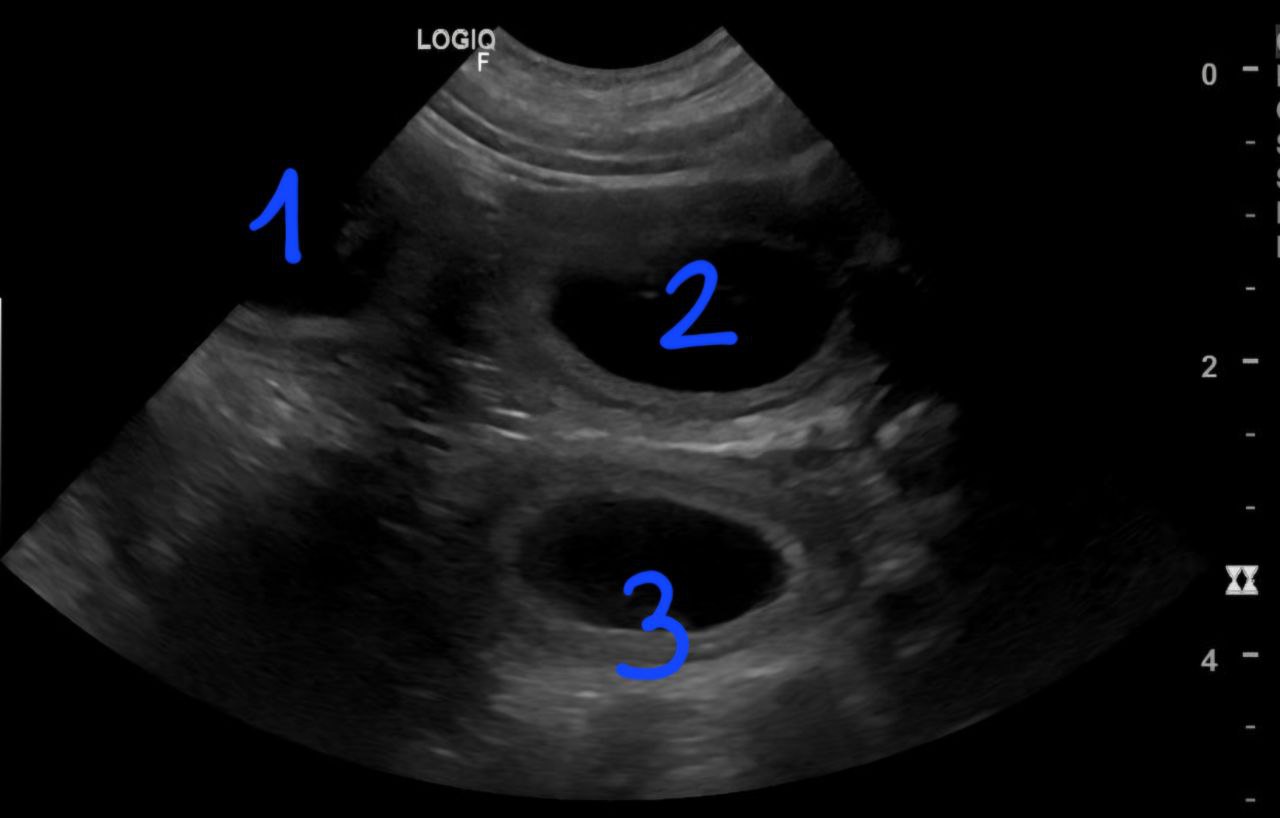

Am 10.12. hatten wir einen Ultraschall-Termin und die schon bereits vermutete Schwangerschaft wurde bestätigt.

Drei Fruchtblasen sind zu sehen.

Hier erkennt man schon einen Welpen.

Die Tierärztin konnte drei Welpen gleichzeitig im Ultraschall erkennen. Wie viele Welpen es aber genau sind, blieb bis zur Geburt eine Überraschung.